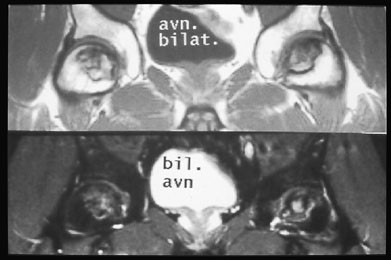

MR-undersøkelse av bekken og hofter blir ofte utført hos pasienter med hoftesmerter hvor konvensjonell røntgen er negativ. MR kan tidlig påvise en osteonekrose og stadieinndele den (fig 13). En klinisk tilstand kjent som beinmargsødem i forbigående osteoporose gir intraktable smerter (10). Dette er en tilstand hvor det er lokalisert osteoporose i caput/collum femoris assosiert med økt væske mellom trabeklene. Røntgenbilder er som oftest normale, spesielt tidlig i forløpet. MR vil vise generelt nedsatt signal på T1-vektet sekvens og betydelig økt signal på STIR-sekvens (fig 14). Tilstanden sees oftest hos middelaldrende menn. Den vedvarer i opptil seks måneder. Årsaken er ukjent.